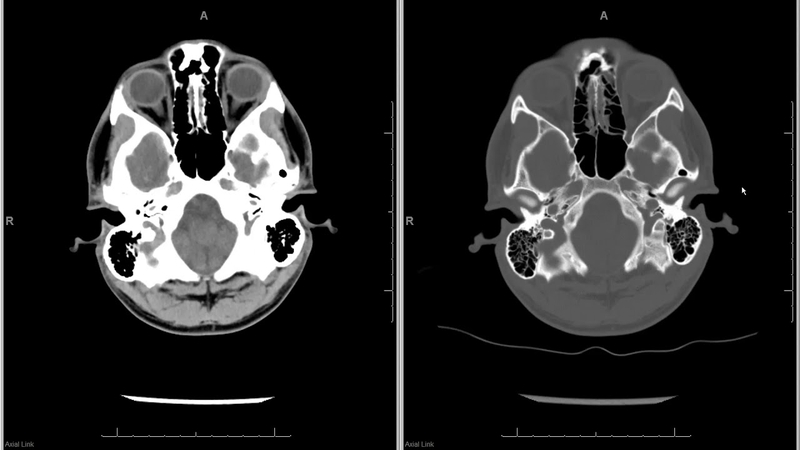

Chụp CT đầu mặt cổ hay chụp cắt lớp vi tính đầu mặt cổ là kỹ thuật dùng tia bức xạ X để chụp ảnh vùng đầu mặt cổ cung cấp hình ảnh 3D bằng công nghệ vi tính hóa. Đây là điểm khác biệt rất lớn giữa chụp CT và chụp X-quang thông thường. Với hình ảnh 3 chiều, chụp CT đầu mặt cổ sẽ giúp bác sĩ có cái nhìn cụ thể và rõ ràng hơn về các cơ quan trong cơ thể con người. Từ đó có cơ sở để đánh giá, chẩn đoán các bệnh lý liên quan vùng đầu mặt cổ.

Trong khi chụp, chùm tia bức xạ X sẽ quay xung quanh vùng đầu mặt cổ để lấy hình ảnh từ nhiều góc khác nhau. Sau đó những hình ảnh này sẽ được hệ thống máy xử lý và tạo ra các hình ảnh cắt ngang (lát cắt) của vùng đầu mặt cổ. Những lát cắt này chính là hình ảnh chụp cắt lớp cung cấp thông tin chi tiết gồm cả mạch máu và mô mềm. Những lát cắt liên tiếp được máy tính thu thập, xếp chồng lên nhau tạo thành hình ảnh 3D. Kết quả chụp CT đầu mặt cổ hỗ trợ đắc lực giúp bác sĩ phát hiện những tổn thương bên trong một cách chính xác nhất.

Phương pháp chụp CT đầu mặt cổ có độ chính xác, tương phản cao, đồng thời phù hợp với nhiều đối tượng. Kết quả chụp cũng mang lại giá trị chẩn đoán cao nhờ khả năng phân biệt mức độ tổn thương thông qua những khác biệt có độ đậm rất nhỏ. Phương pháp này cũng cho phép chụp được nhiều góc độ và nhiều lát cắt, tránh bỏ sót những tổn thương nhỏ.